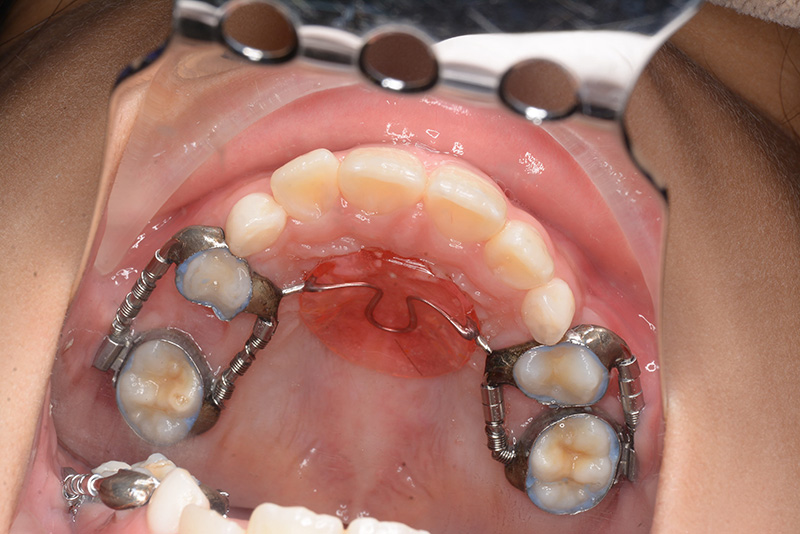

| 使用装置 | GMD、Nanceホールディングアーチ | ||||||

| パノラマ所見 | 上顎両側6、特に左側6は近心傾斜が認められ、両側5の萌出スペース不足が認められた。 |

| 批評・予后 | 早期に6の遠心移動を行いナンスのホールディングアーチにて保隙をした結果、5は良好な状態で萌出できたように思う。 今後は永久歯列完成まで経過観察を行っていく予定である。 |